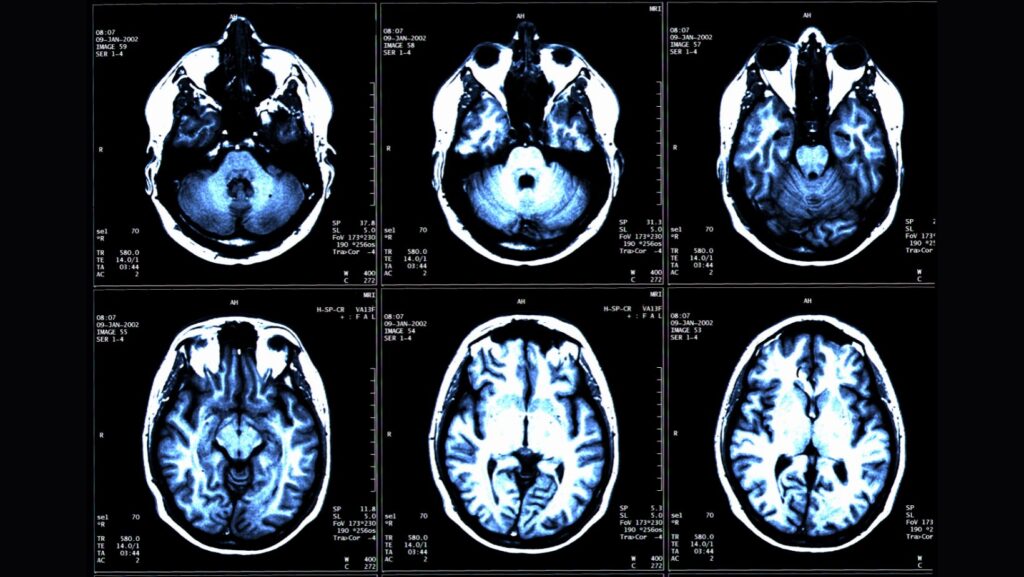

연구팀은 이 연구에서 뇌의 구조적 MRI 영상의 부위별 부피를 기반으로 추정한 뇌 나이와 전신 MRI로 측정한 총근육량과 내장지방, 피하지방 사이의 연관성을 인공지능 알고리즘으로 분석했다.

이들은 4개 지역 거주자 1천164명(평균 나이 55.17세)을 대상으로 전신 MRI를 촬영하고 이를 지방과 체액, 근육 등이 다른 색으로 보이게 하는 기법과 결합해 총근육량과 내장지방 피하지방, 뇌 나이를 정량화했다.